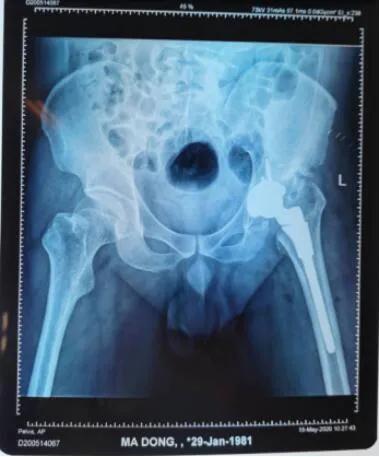

术后。

经过一系列检查,确诊为“左髋关节化脓性关节炎后遗症”,最佳的治疗方案是全髋关节置换术。

从拍摄的影像片看出,马先生左侧股骨头已基本消失并且明显上移,错位明显,已与“假”的髋臼形成“假”关节。

术前。